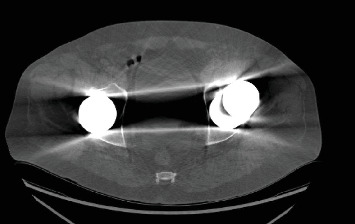

Introduction: Total hip arthroplasty (THA) is a commonly performed and highly successful surgical procedure. Metal-on-metal (MoM) THA implants were introduced two decades ago and subsequently recalled due to high early revision rates. Acetabular cup erosion and fragmentation secondary to chronic edge loading causing delayed instability are rare but devastating complications of MoM THA warranting expeditious revision surgery. Case Presentation: We report a 70-year-old male with a history of bilateral MoM THA who presented with left hip instability. In addition to the radiographic and clinical features of hip instability, macroscopic examination at revision surgery revealed extensive erosion and fragmentation of the antero-superior margin of the implanted cup, osteolysis, and widespread metallosis of the periarticular soft tissues. Discussion: This case highlights a significant adverse complication of MoM THA. Despite the industry's wide discontinuation and recall of these implants, MoM hip arthroplasty implants are present in many patients, who are all at risk of developing similar complications. Guidelines for the surveillance and treatment of both symptomatic and asymptomatic MoM THAs have been reported, although ambiguity remains in the optimal approach for managing patients with existing MoM THA. Conclusion: Failure of MoM hip arthroplasty is most commonly the result of adverse reaction to metal debris. We present a novel mechanism of failure in a patient presenting with late instability due to asymmetric wear of the MoM bearing surface.. While it is uncertain whether early intervention in this patient may have prevented this complication, arthroplasty surgeons should be aware of the various modes of failure for MoM hip implants, as expeditious revision surgery is often required.

全髋关节置换术(THA)是一种常见且非常成功的外科手术。金属对金属(MoM) THA植入物在20年前引入,随后由于早期翻修率高而被召回。髋臼杯糜烂和骨折继发于慢性边缘负荷导致迟发性不稳定是罕见的,但毁灭性的并发症需要快速翻修手术。病例介绍:我们报告一位70岁男性,有双侧MoM THA病史,表现为左髋关节不稳定。除了髋关节不稳定的影像学和临床特征外,翻修手术时的宏观检查显示植入杯前上缘广泛糜烂和碎裂,骨溶解,关节周围软组织广泛金属化。讨论:本病例强调了MoM THA的一个重要的不良并发症。尽管业界广泛停止和召回这些植入物,MoM髋关节置换术植入物存在于许多患者中,他们都有发生类似并发症的风险。有报道了有症状和无症状MoM THA的监测和治疗指南,尽管对于现有MoM THA患者的最佳治疗方法仍然不明确。结论:MoM髋关节置换术失败最常见的原因是金属碎片的不良反应。我们提出了一种新的失败机制,在病人表现出晚期不稳定,由于不对称磨损的MoM承载表面。虽然尚不确定该患者的早期干预是否可以预防这种并发症,但关节置换外科医生应该意识到MoM髋关节植入物的各种失败模式,因为通常需要快速翻修手术。